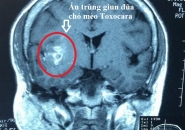

Dấu hiệu nào nhận biết bệnh giun đũa chó mèo Toxocara?

Những điều cần biết về bệnh giun đũa chó mèo

Dấu Hiệu Nhận Biết Sán Lên Não